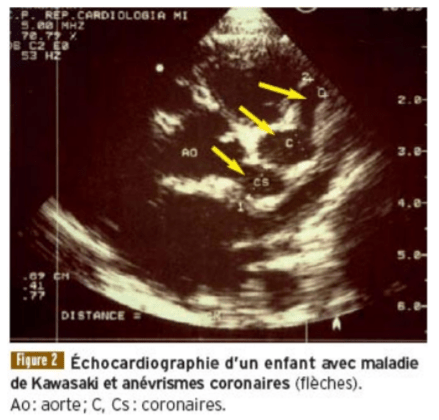

On observe une recrudescence de formes atypiques de la maladie de Kawasaki depuis le mois d’avril 2020 en Grande Bretagne, Italie, France, Espagne et Belgique, c’est-à-dire précisément les pays d’Europe les plus touchés par le Covid-19. Ces symptômes sont des douleurs abdominales, des troubles gastro-intestinaux et une inflammation cardiaque chez les enfants âgés de 2 à 10 ans, sans antécédents connus. Dans les formes graves, elle se traduit par une inflammation des artères, notamment coronaires, susceptible d’aboutir à un infarctus du myocarde.